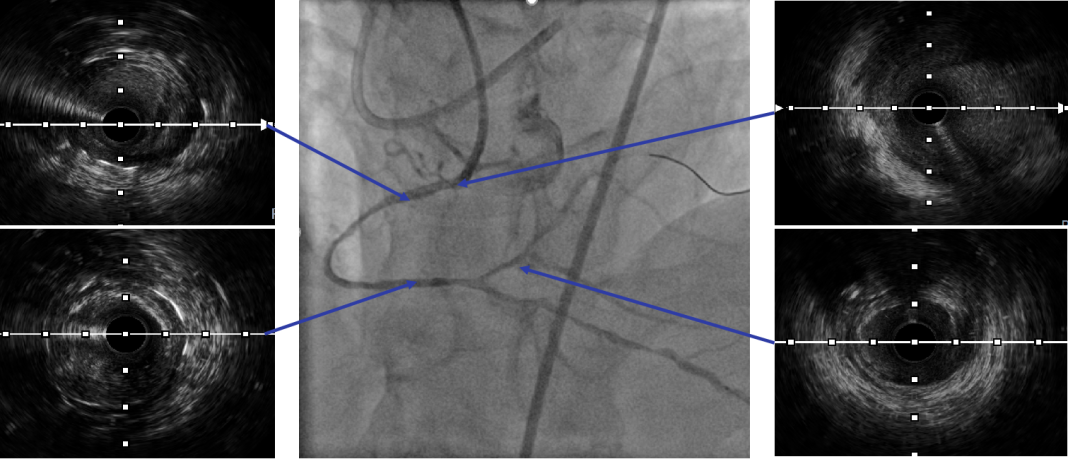

建立轨道后,交换为Runthrough 导丝后,行IVUS检查证实导丝位于血管真腔。

利用IVUS精确选择支架落脚点。

IVUS显示支架贴壁良好,未见夹层,RCA中远段MSA 7.41mm²,术毕。

血管内成像可以促进CTO再通、改善长期疗效。